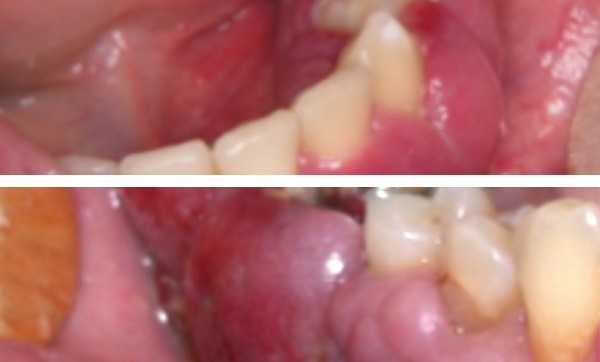

Examen clinique. Sous le maquillage, l’inspection exo-buccale révélait sur la joue gauche une lésion angiomateuse de couleur rouge. L’examen endo-buccal montrait un accroissement gingival violine qui s’étendait de 31 à 36. La palpation mettait en évidence une lésion légèrement molle, non pulsatile, saignant facilement.

Examen paraclinique. Une biopsie a été réalisée et l’examen anatomopathologique a révélé de nombreuses cavités vasculaires de taille variable dont la paroi mince était constituée d’un simple endothélium ; cet aspect est compatible avec celui d’une malformation veineuse.

Synthèse. La classification des lésions vasculaires distingue les hémangiomes du nourrisson qui régressent spontanément et les malformations vasculaires qui perdurent. Parmi les malformations vasculaires, on différencie : les malformations vasculaires à flux lent (capillaires, veineuses et lymphatiques) et les malformations vasculaires à flux rapide (artério-veineuses). Les malformations vasculaires se manifestent par une coloration bleutée, violacée ou rouge de la muqueuse buccale. Les plus fréquentes sont les malformations veineuses. La patiente présentait une malformation…